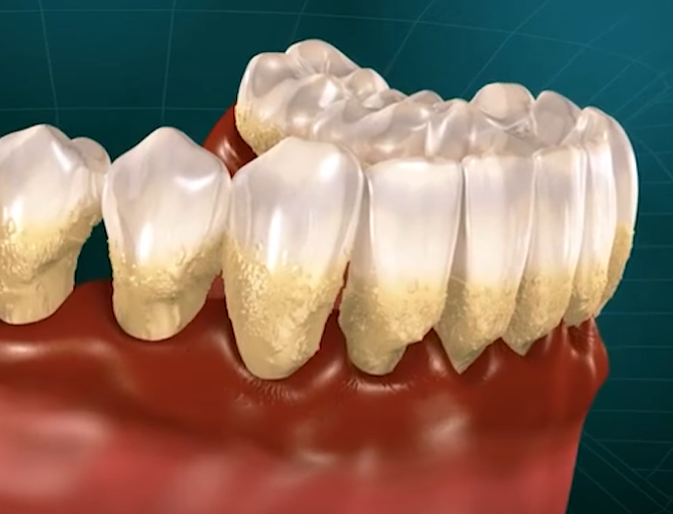

치주염과 잇몸 내려 앉음 [잇몸퇴축]

치주염은 잇몸의 주요 질환으로, 치조골(잇몸을 지지하는 뼈)을 파괴합니다.

잇몸은 치조골의 상태를 따라가므로, 치조골이 손상되면 잇몸도 함께 퇴축하게 됩니다.

치과의사는 정기적인 스케일링과 철저한 치아 관리를 통해 치주염을 예방하고 잇몸 퇴축을 방지할 수 있다고 조언합니다.